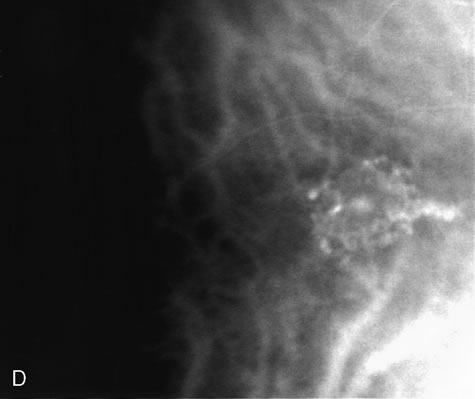

Fig. 23. Central serous chorioretinopathy with multiple retinal pigment epithelium (RPE) detachments. A. This red-free photograph demonstrates the large macular neurosensory detachment. B. Early-phase fluorescein angiogram reveals three hyperfluorescent RPE defects. C. These defects do not contribute evenly to the neurosensory detachment. Although the superior macular defect is leaking fluorescein into the subretinal space intensely, the defect near the optic nerve head along the superotemporal arcade is not leaking fluorescein and does not have an overlying neurosensory detachment. D. After treatment of the RPE detachments, the neurosensory detachment has resolved. (Courtesy of Dr. Kenneth G. Noble.)